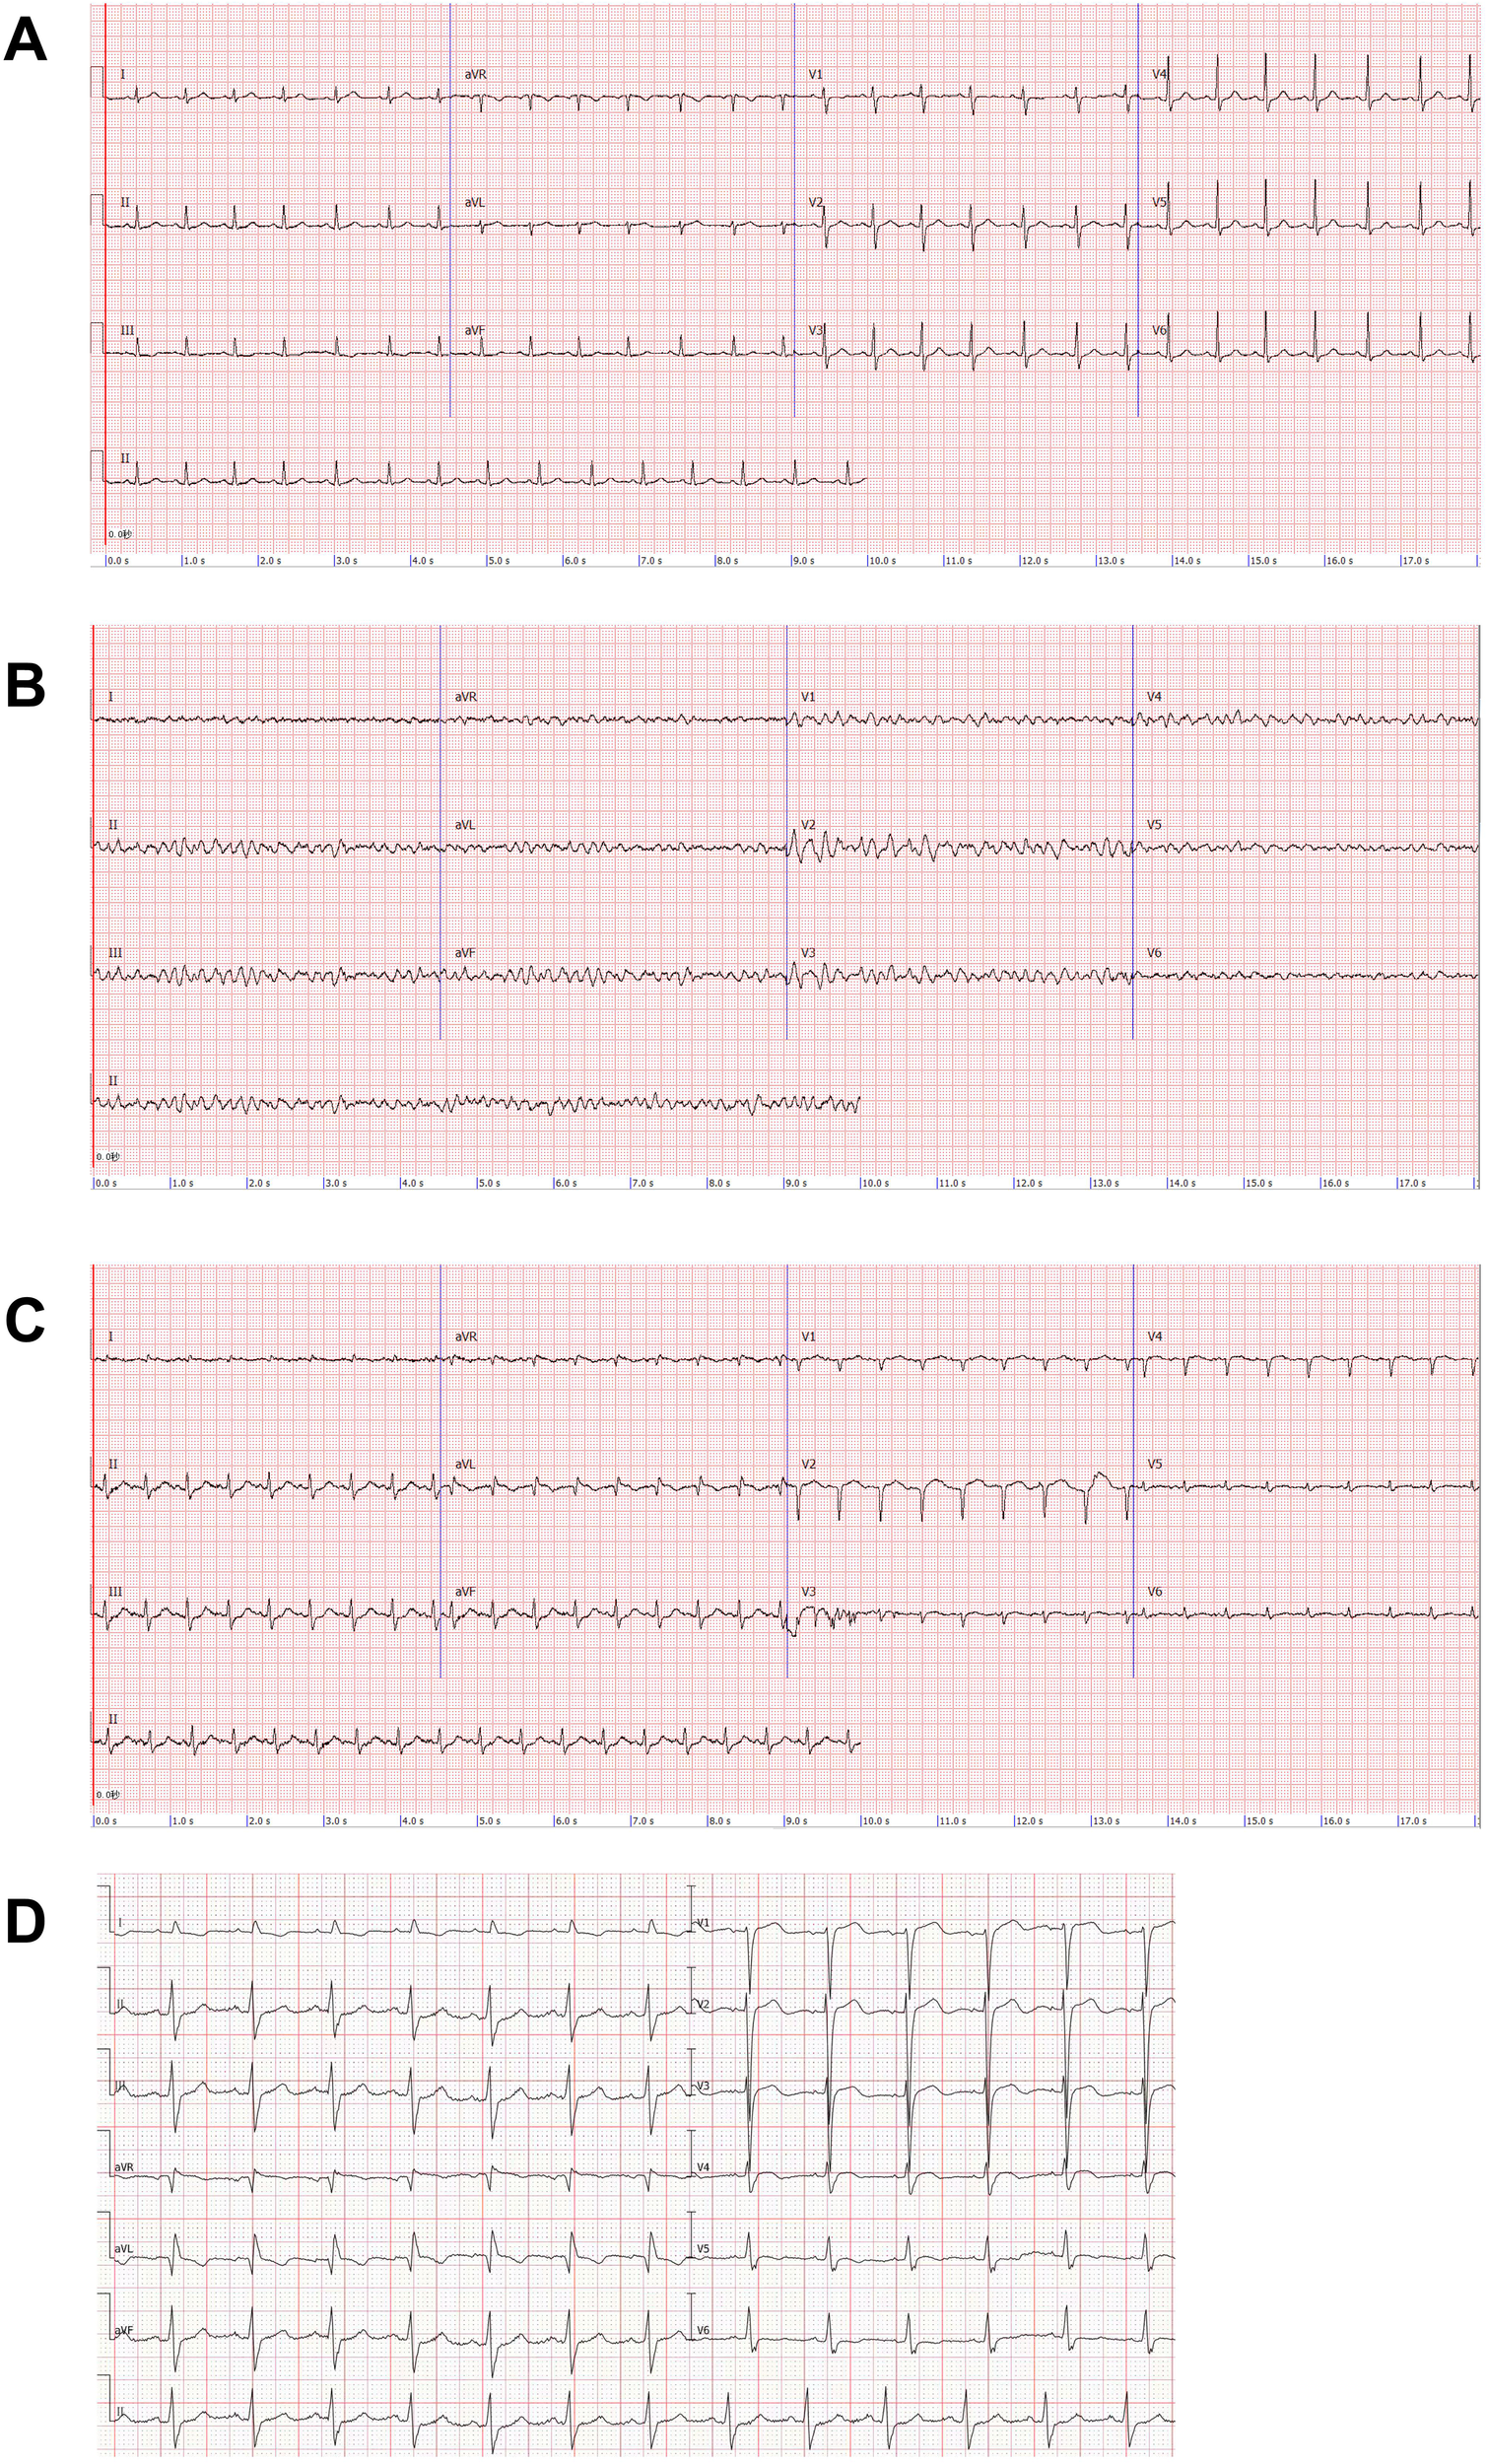

Figure 1

Electrocardiogram (ECG). (A) Patient's pre-surgical ECG. (B) Patient develops ventricular fibrillation after shock. (C) ECG after ECMO implantation: poor R-wave progression in the anterior wall leads, abnormal Q-waves in the high lateral wall leads, T-wave alterations, and a decrease in the voltage of the QRS wave in the left thoracic lead. (D) ECG of the patient one month after receiving unroofing.

The patient was transfused with blood cells and balanced crystalloids after surgery. Six hours later, the patient demonstrated weakness and chest tightness, with a blood pressure of 78/34 mmHg. We considered this a manifestation of hypovolemic shock; however, continuous blood transfusion and fluid resuscitation could not raise the blood pressure. Subsequently, the patient manifested respiratory and circulatory failure, and the electrocardiogram (ECG) demonstrated ventricular fibrillation (Figure 1). We immediately initiated cardiopulmonary resuscitation (CPR) and subsequently performed electrical defibrillation. After two minutes of CPR, sinus rhythm was restored and her blood pressure increased to 81/40 mmHg. After 12 min, the patient's heart rate dropped to 46/min, her blood pressure was undetectable, and her aortic pulsation disappeared; thus, we performed extracorporeal cardiopulmonary resuscitation on her. VA-ECMO (left femoral vein-right femoral artery) was implanted and the initial ECMO centrifugal pump speed was 3,490 rpm and the support flow rate was 3.36 L/min. The patient was anticoagulated with heparin, maintaining the activated partial thromboplastin time between 60 s and 80 s. A distal perfusion catheter was placed to direct a proportion of the returned oxygenated blood flow from the ECMO circuit to the distal right femoral artery. The patient's blood temperature was maintained below 36°C for cerebral resuscitation. Continuous renal replacement therapy was initiated via the ECMO circuit due to the patient's volume overload, anuria, severe metabolic acidosis, and acute kidney injury. At this time, the patient's ECG revealed myocardial ischemia (Figure 1), and the cardiac ultrasound revealed diminished myocardial contractile motion in the left ventricle with a left ventricular ejection fraction (LVEF) of 30% and a pulmonary artery pressure of 61 mmHg. The patient regained consciousness on day 2. We began administering digoxin on the fourth day of the ECMO treatment.